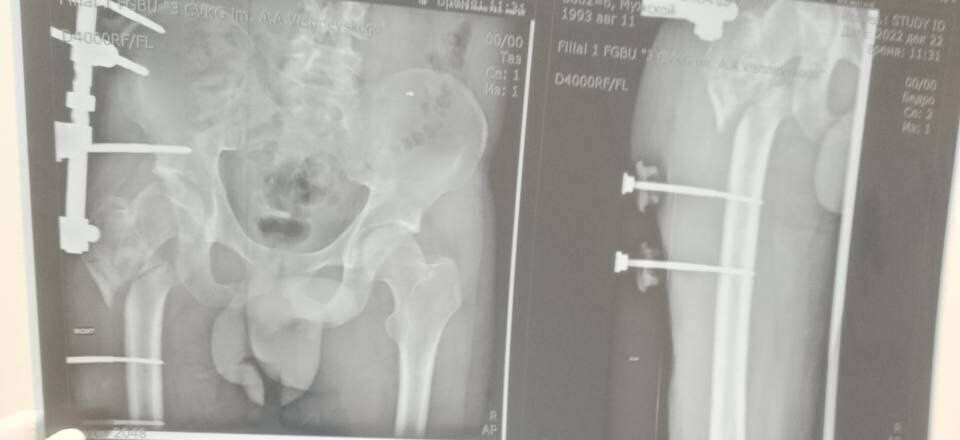

Сержант 1993 года рождения, мобилизованный 25 февраля 2022 года, получил тяжелое ранение правого бедра 28 августа 2022 года под ракетным обстрелом на Херсонщине. За три с половиной года он прошел лечение в десяти госпиталях, включая Москву и Санкт-Петербург. В июле 2024 года боец, награжденный медалью «За отвагу», был уволен по здоровью. Из-за множественных операций и повреждений его правая нога стала короче левой на 8–9 см.

«Требовалось чудо инженерной и хирургической мысли. Чудо произошло 5 марта 2026 года в Луганске. В Луганской республиканской клинической больнице бригада травматологов-ортопедов провела операцию, которая стала финальным аккордом этой долгой истории. Вместо стандартной замены сустава пациенту выполнили сложнейшее вмешательство с использованием ревизионных систем эндопротезирования, в ЛНР такую операцию провели впервые», — рассказала Пащенко.

Хирурги восстановили ось конечности и компенсировали укорочение, работая в рубцово-измененных тканях после множества предыдущих операций, устранив очаги инфекции и «собрав» сустав заново с помощью специальных ревизионных компонентов.